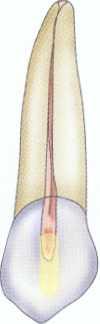

Maxillary Incisors

In uncomplicated cases, both maxillary central and lateral incisors share a common triangular-shaped access from the lingual surface of the tooth. The classic access design places the access centrally on the lingual surface between the incisal edge and the cervical edge7 ( Figure 2-14). This design is reflective of the poor restorative choices available in the past as well as the limited options for "hiding" the access more cervically. Such a design results in a much larger amount of dentin removal at the lingual cervical edge to gain straight-line access. With improved esthetic bonded composites, the classic access form can be modified by placing it considerably more incisally (Figure 2-15). The initial penetration should be approximately in the middle of the lingual surface of the tooth, not just above the cingulum as has been previously described.' After locating the canal, the clinician uses a long, tapered diamond to extend the access even further incisally and laterally. An additional modification for use with rotary instrumentation is to slightly notch the middle of the incisal extent of the access (see Figure 2-15). This allows even better straightline access and greatly decreases the potentially catastrophic cervical flexure of the rotary instruments that can contribute to premature, unexplained fracture.

In anterior teeth the clinician must take care to remove all the coronal tissue and debris from the chamber. Material left in the chamber can cause tooth discoloration. The pulp horns are common locations for residual tissue (Figure 2-16).